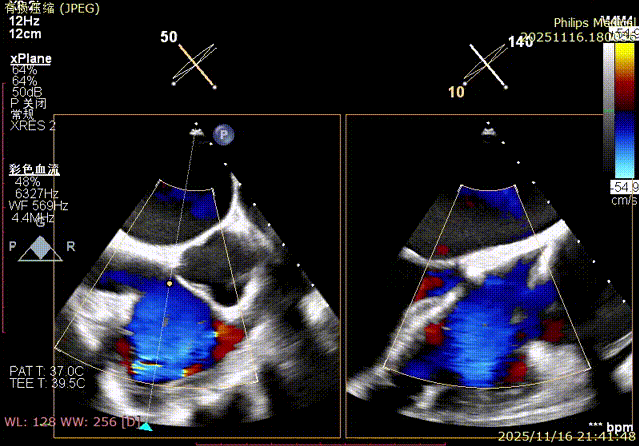

Echocardiographic Assessment: Echocardiography revealed left atrial enlargement. The left atrial appendage (LAA) orifice was 32mm with no thrombus inside. Tricuspid regurgitation was extreme (average vena contracta 18mm). Regurgitant jets were located at the anterior-septal, central, and posterior-septal commissures, with a central gap measuring approximately 13x5.9mm. The annulus was mildly dilated (average diameter 43mm). The tricuspid leaflets showed thickening and degenerative changes.

The entire procedure was guided by both Transesophageal Echocardiography (TEE) and Digital Subtraction Angiography (DSA).

Immediate intraoperative echocardiographic verification showed that the tricuspid regurgitation area was significantly reduced from a preoperative grade of 5+(pre-op) to 2+(post-op), downgrading the severity from extreme to mild-moderate.

Comparison of TR regurgitation severity: reduced from 5+ to 2+

preoperative

postoperative

- TR Severity Comparison: Reduced from 5+ to 2+.